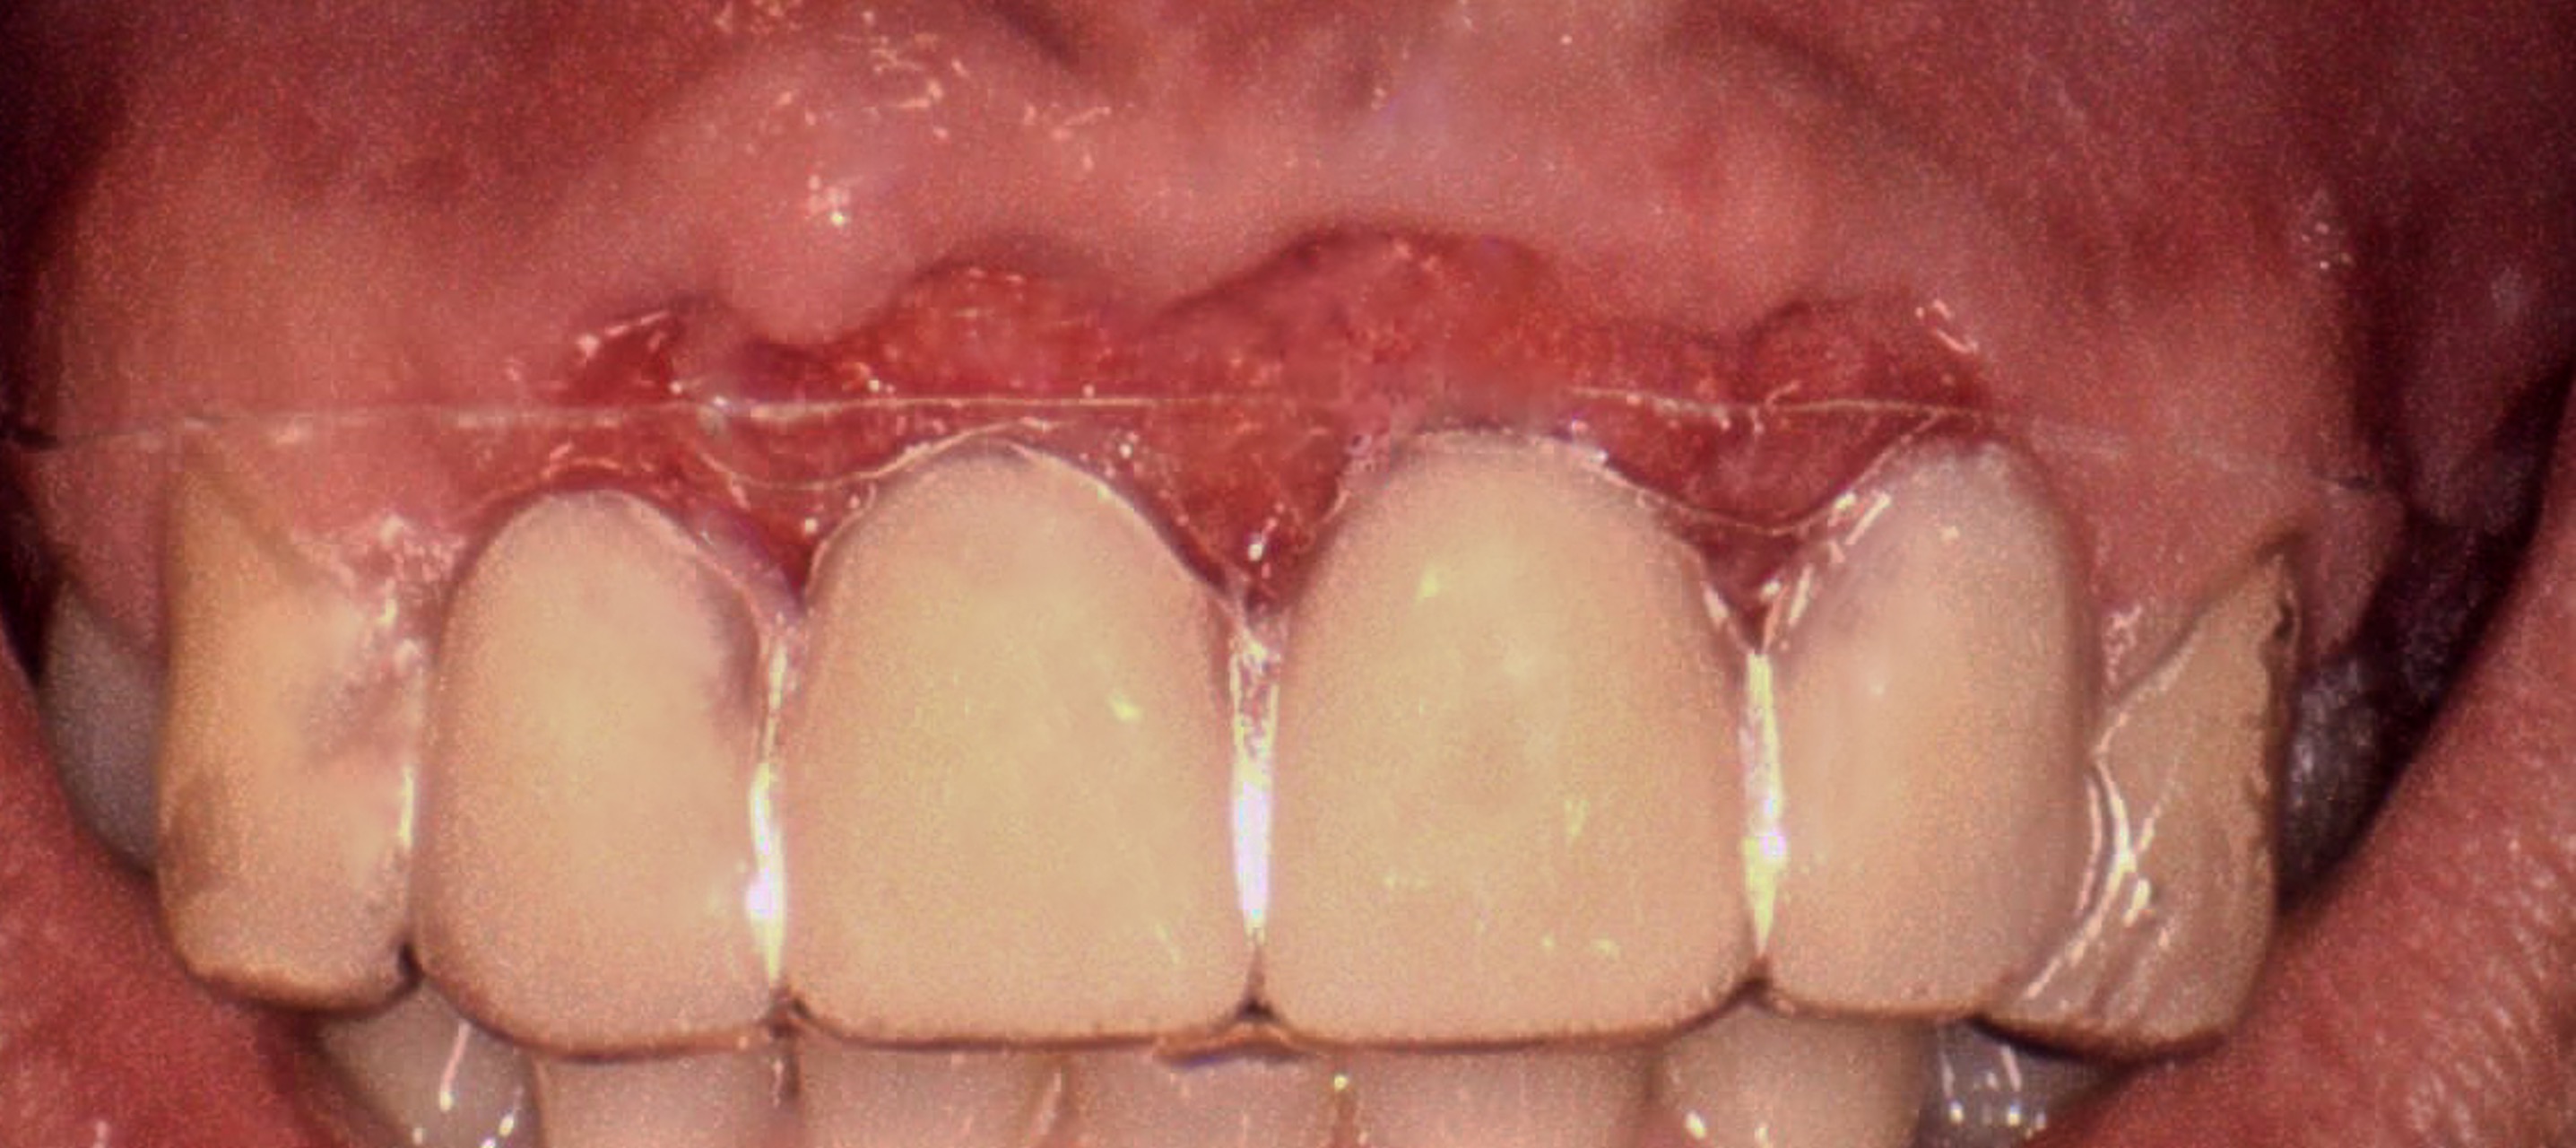

December 07, 2023Atraumatic extraction of teeth #7–10 with thorough debridement of infected tissue and immediate GBR to rebuild the anterior ridge and preserve the smile line.

- Use of provisional restorations to shape soft tissue contours and maintain esthetics while the implants and regenerated bone matured.